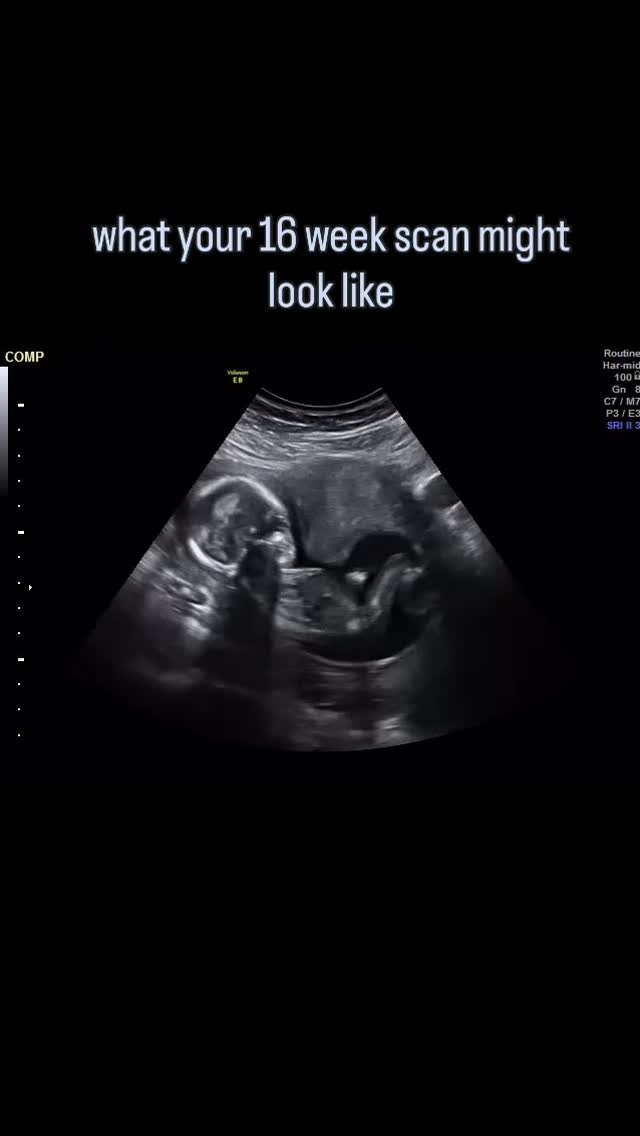

BabyScan UK offers a range of packages in revolutionary baby scanning - giving parents the chance to see digital 3D and 4D live images of their child, which can be recorded on USB at various stages in pregnancy.